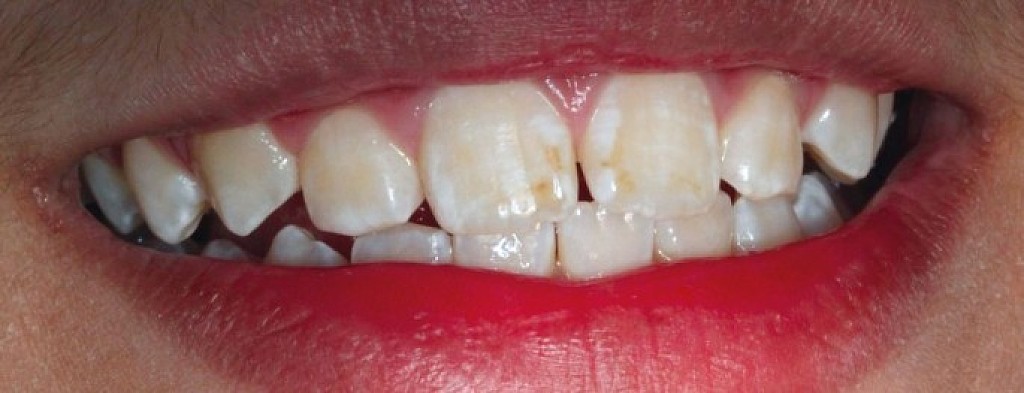

What Is Enamel Hypoplasia?

Enamel is the hard, protective outer layer of your teeth. Enamel hypoplasia is a defect of the enamel that only occurs while teeth are still developing. Still, it can affect both baby teeth and permanent teeth. The condition results in thin enamel, which makes your teeth vulnerable to dental decay.

The visual signs of enamel hypoplasia include white spots, pits, and grooves on the outer surface of the teeth.

Tooth enamel is the hardest substance in your body, but it doesn’t contain living cells and can’t repair itself or improve on its own. So, if you or your child has enamel hypoplasia, you’ll need to have a dentist monitor your teeth and act quickly to repair problem areas.

What are the symptoms?

Some of the signs of enamel hypoplasia are obvious, but others are more difficult to detect and may not be noticeable until they cause major dental problems. Having thin tooth enamel can lead to:

pits, tiny groves, depressions, and fissures

white spots

yellowish-brown stains (where the underlying layer of dentin is exposed)

sensitivity to heat and cold

lack of tooth contact, irregular wearing of teeth

susceptibility to acids in food and drink

retention of harmful bacteria

increased vulnerability to tooth decay and cavities.

What causes it?

Defective enamel development can be the result of an inherited condition called amelogenesis imperfecta, or congenital enamel hypoplasia, which is estimated to affect about 1 in 14,000 people in the United States. This condition can also cause unusually small teeth and a variety of dental problems. Congenital enamel hypoplasia can happen alone or as part of a syndrome affecting other parts of the body.

Other hereditary syndromes that can cause enamel hypoplasia are:

Usher syndrome

Seckel syndrome

Ellis-van Creveld syndrome

Treacher Collins syndrome

otodental syndrome

22q11 deletion syndrome (velocardiofacial syndrome)

Heimler syndrome

Enamel hypoplasia can also result from prenatal issues such as:

maternal vitamin D deficiency

maternal weight gain

maternal smoking

maternal drug use

lack of prenatal care

premature birth or low birth weight

Environmental factors and other problems in infancy that can cause enamel hypoplasia include:

trauma to the teeth

infection

calcium deficiency

deficiencies of vitamins A, C, or D

jaundice, liver disease

celiac disease

cerebral palsy due to maternal or fetal infection.

How is it treated?

Early screening and diagnosis are crucial. That’s why children should see a dentist sometime between the appearance of their first tooth and their first birthday.